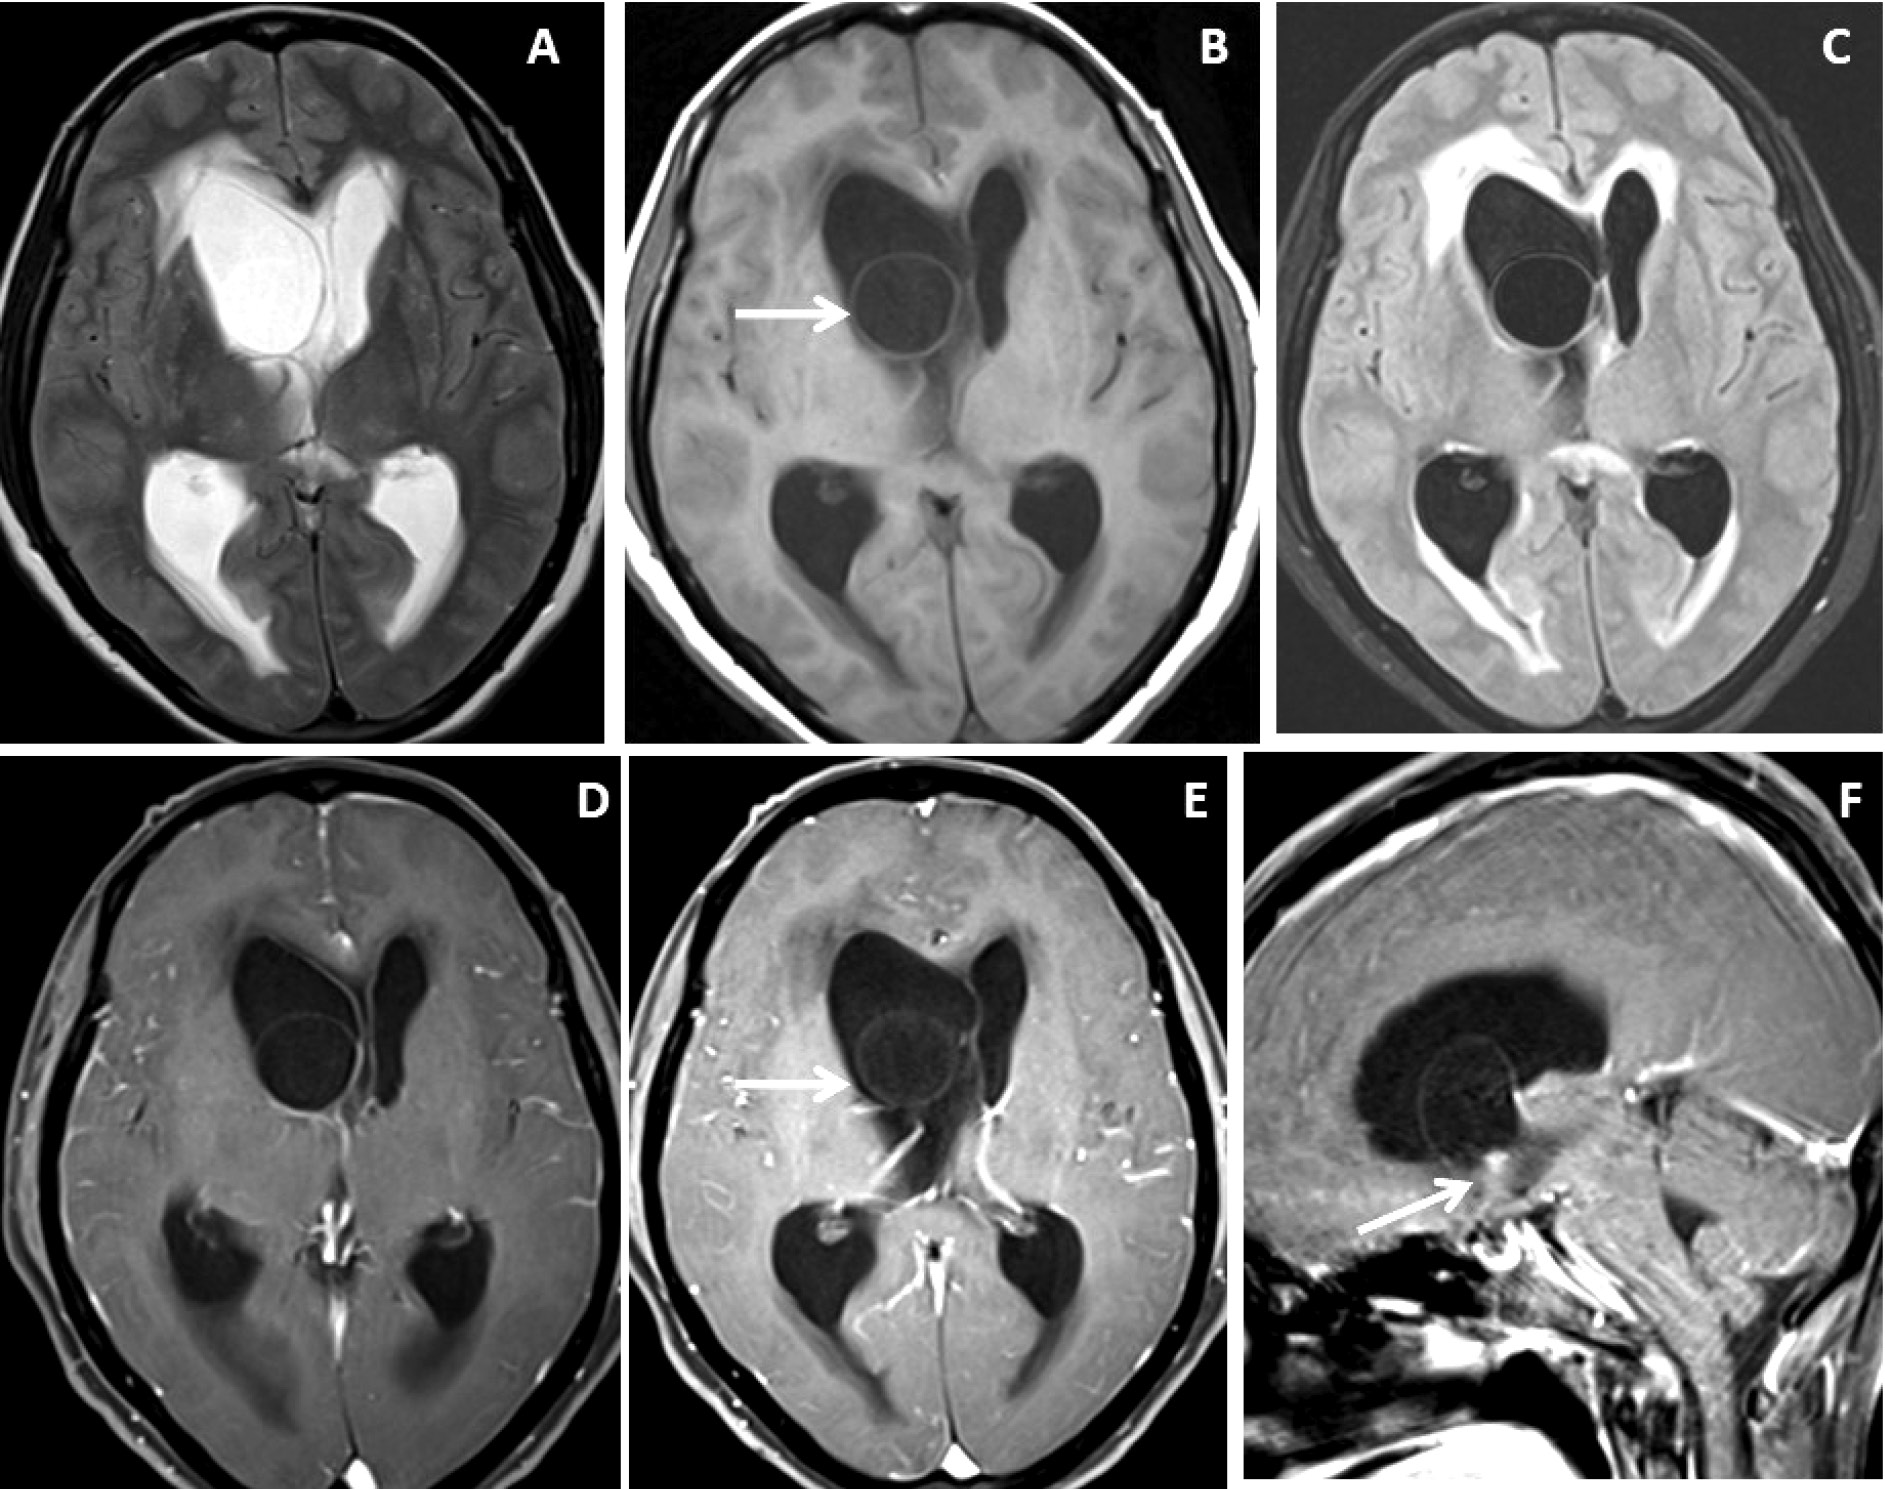

Figure 3. Brain magnetic resonance imaging of 25 years male with headache. (A-B) Axial T2WI and FLAIR images show distension and dilatation of the fourth ventricle with minimal periventricular CSF seepage. Variable signal intensity cystic lesions are seen within the fourth ventricle on the FLAIR image (arrow). (C-D) Axial and coronal heavily T2W images show multiple thin-walled hyperintense cystic lesions (arrows) with less hyperintense CSF signal within the 4th ventricle with variable sizes irregular nodules within. (E-F) Axial and sagittal T1W post-contrast image shows thin smooth enhancement of the intraventricular cyst (arrow) with enhancing irregular nodules. Post-contrast enhancement is also seen along the ependymal lining of the 4th ventricle, in posterior and inferior aspects.

Very thin smooth cyst wall enhancement was observed in 9(90%) patients (Figure 1 and 2) and irregular peripheral rim-like wall enhancement with an irregular nodule in 1(10%) patient. Ventricular ependymitis with smooth to irregular ependymal lining enhancement was observed in 7(70%) patients (Figure 3). Presence of hydrocephalus detected in 8(80%), where MRI revealed asymmetrical enlargement of lateral ventricle with periventricular CSF seepage in 4(40%) patients (Figure 1), dilatation of 3rd ventricle in 2(20%) patients and ballooned 4th ventricle in another 2(20%) patients(Figure 4).

Four (40%) patients were treated conservatively with cysticidal drugs only and 6 (60%) patients were treated surgically followed by cysticidal drugs. Craniotomy with micro-surgical resection was done in 2 patients with 4th ventricular neurocysticercosis and endoscopic approach in another 4 patients with lateral and 3rd ventricular neurocysticercosis. On follow-up, 8(80%) patients show complete healing of the intraventricular neurocysticercosis, 1 (10%) patient showed disease recurrence and another 1 (10%) patient died.